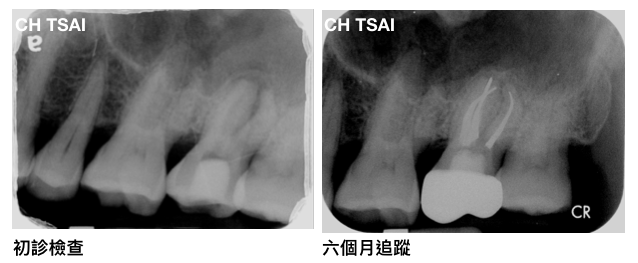

陳先生因為在他家診所進行根管治療,經過多次治療後症狀仍然沒有改善,他家診所醫師建議他尋求牙髓病專科醫師的協助。

來診時,主觀症狀陳先生覺得還有些微咬痛,並且還有些許鼻竇炎的症狀;臨床檢查也有些壓痛和敲痛的情形。

根管治療結束之後,蔡醫師也建議病患製作牙冠補綴物來保護脆弱的齒質。這時陳先生的症狀已經完全改善了,補綴物製作完成後,就剩下清潔及回診追蹤囉!六個月時,也可以發現原先呈現雲霧狀的鼻竇白影,也慢慢的回復乾淨了。